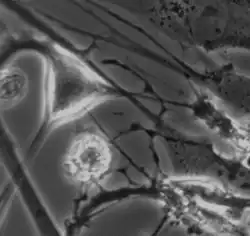

The myenteric plexus shown in the muscular layer of the gastrointestinal tract

Interstitial cell of Cajal shown in the myenteric plexus of a mouse embryo